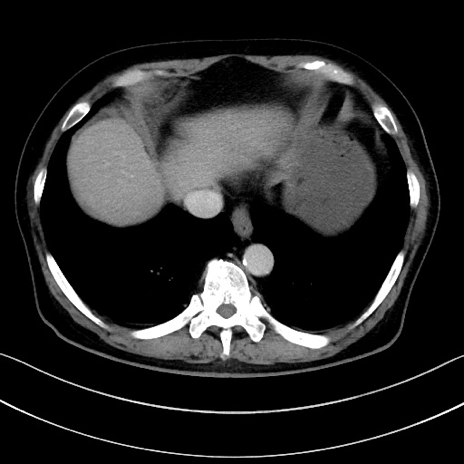

症例15(横断像)

【症例】70歳代男性

【主訴】腹痛

【現病歴】今朝から腹痛あり。全体的に痛い。特に左上の方。排ガスが今日はない。冷や汗が出る。

【既往歴】直腸癌術後

【身体所見】左側腹部〜上腹部に圧痛あり。腹膜刺激症状明らかなではない。軽度反跳痛。左下腹部に術後瘢痕あり。

【データ】WBC 7700、CRP 0.02